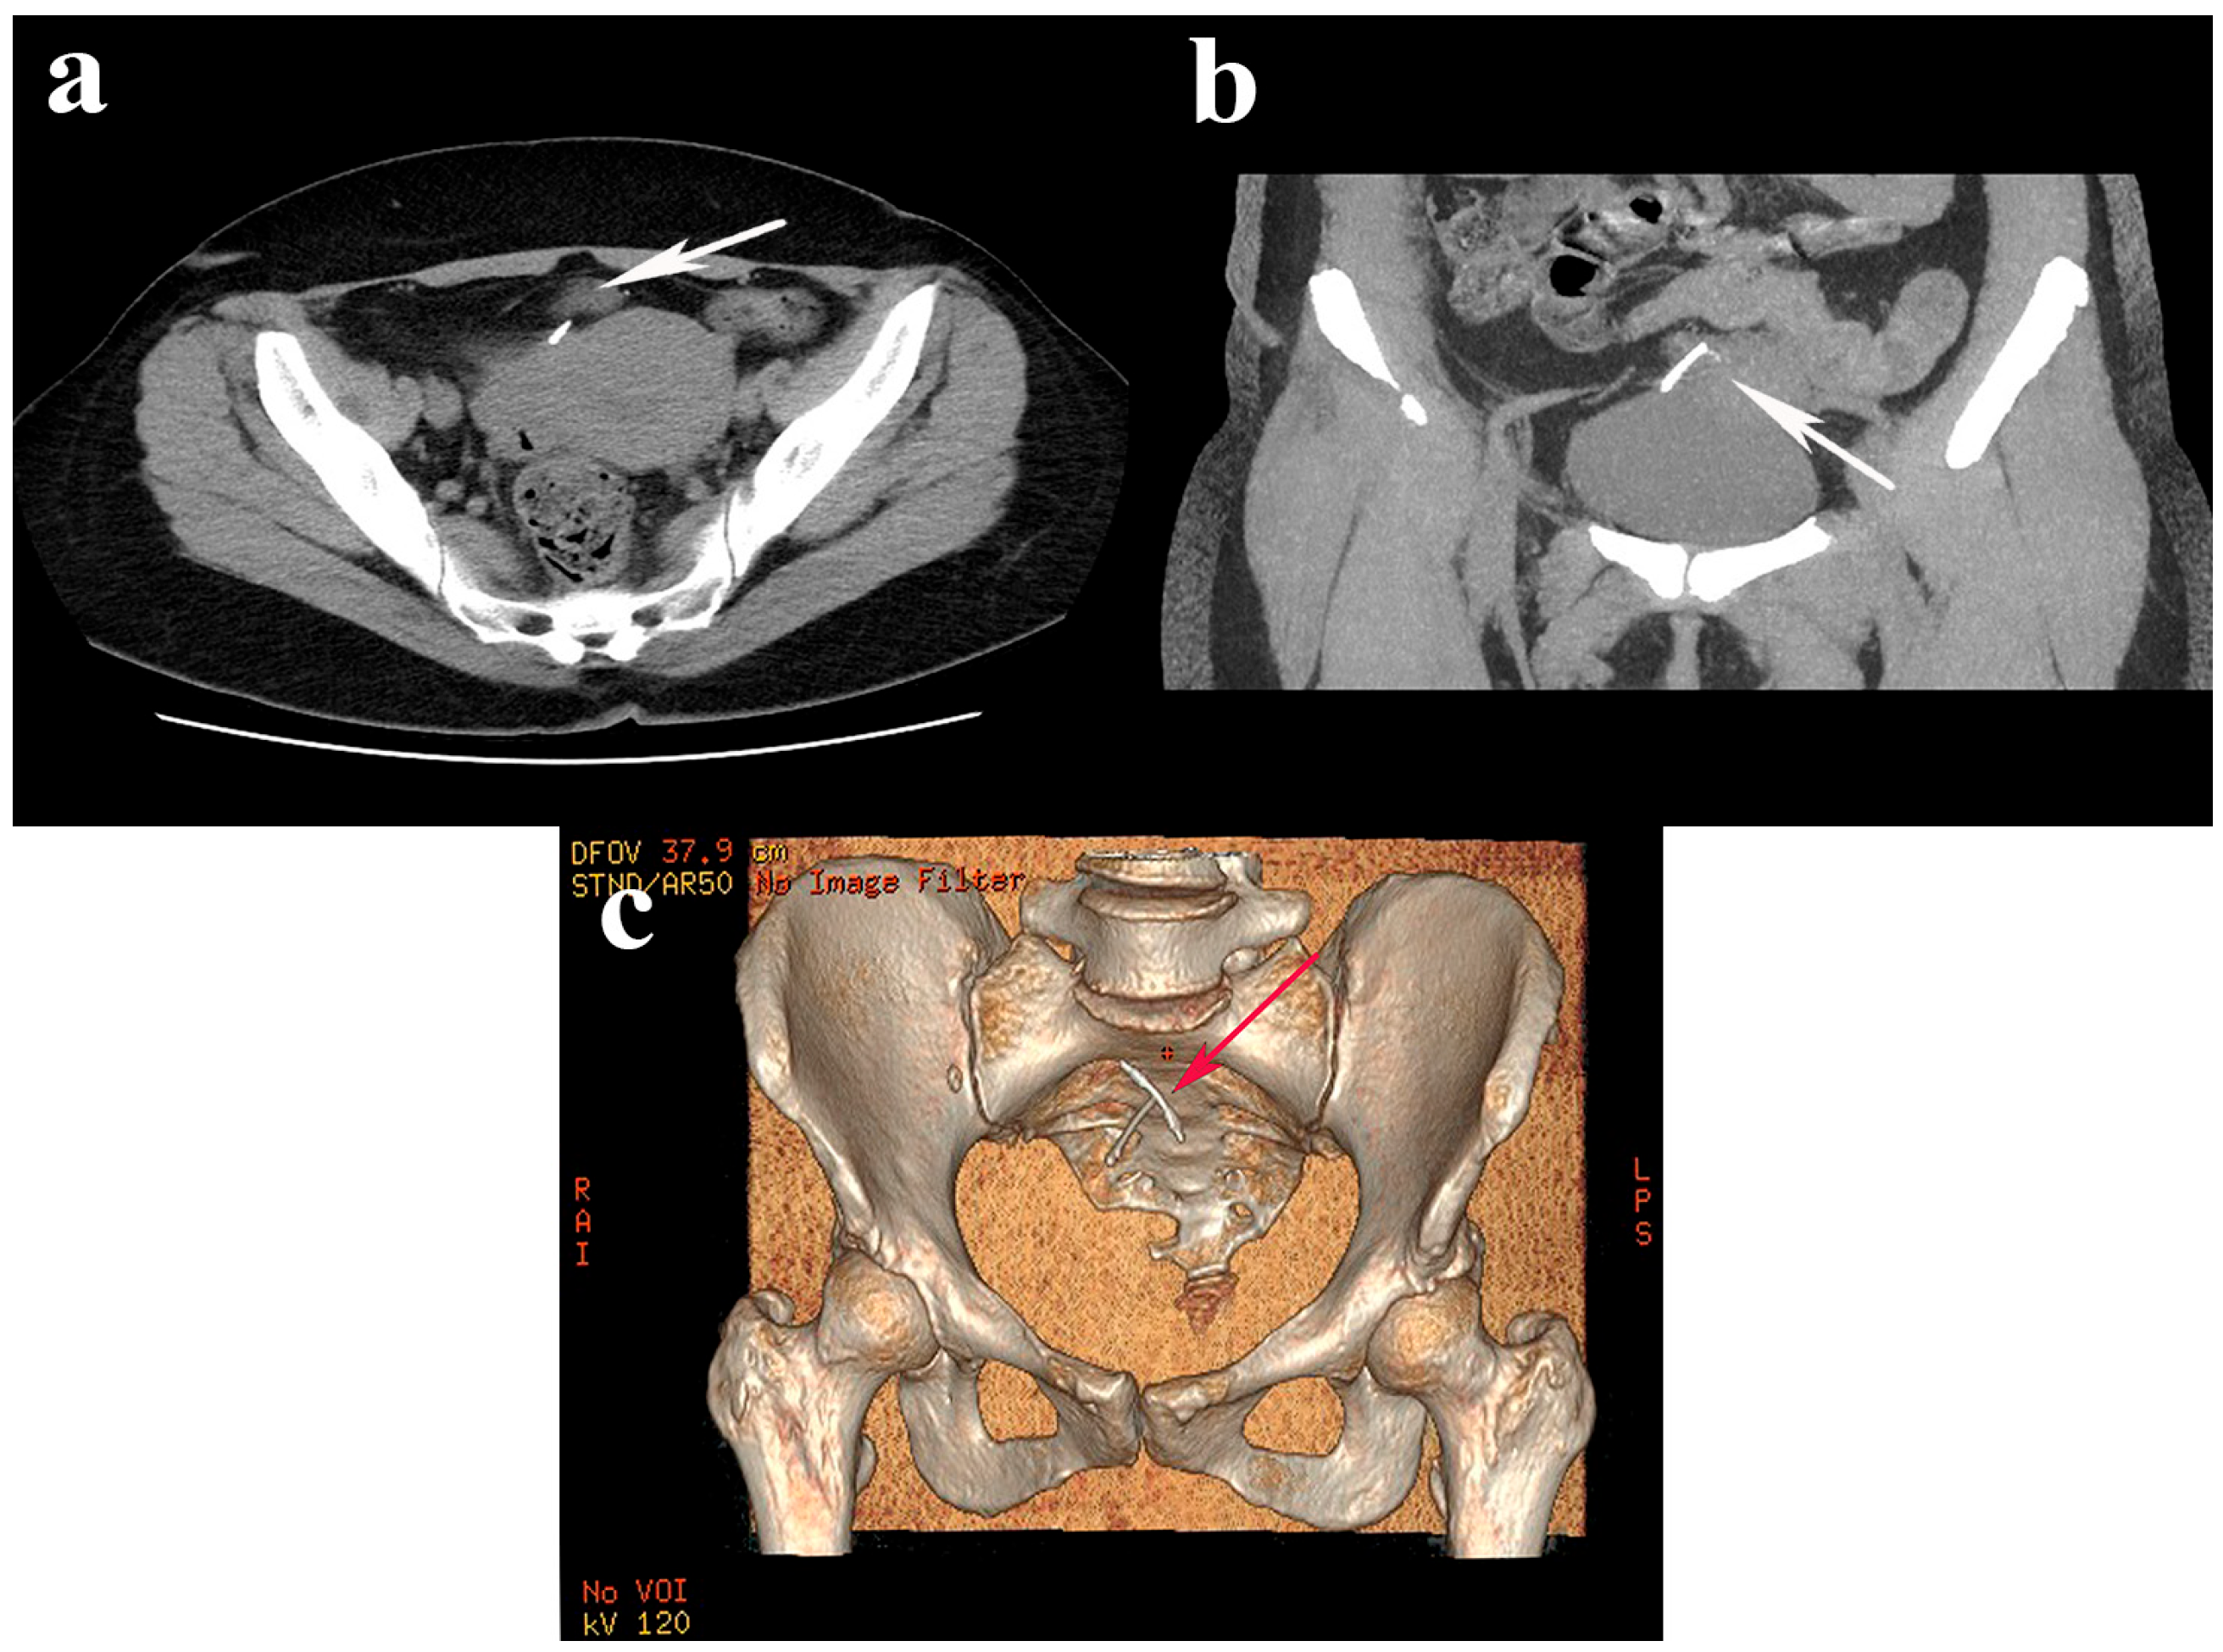

| Our case, 2023 | 55 | Asymptomatic during investigations for lumbar discopathy | 19 yrs | 2 | NS | X-ray, US, CT scan, hysteroscopy/laparoscopy | Submucosa of the bladder; pelvic mass of adhesions between omentum, sigmoid, bladder | Laparoscopic IUD removal after adhesiolysis and cystorrhaphy | Favorable |